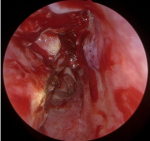

Intervention: conchoplastie endoscopique droite sous anesthésie générale. Résection partielle de la paroi latérale du cornet avec préservation de la muqueuse médiale. Objectif: réduction du volume tout en maintenant la fonction physiologique (Figure 3).

Figure 3 : image endoscopique peropératoire montrant la conchoplastie droite associée à une turbinoplastie inférieure homolatérale